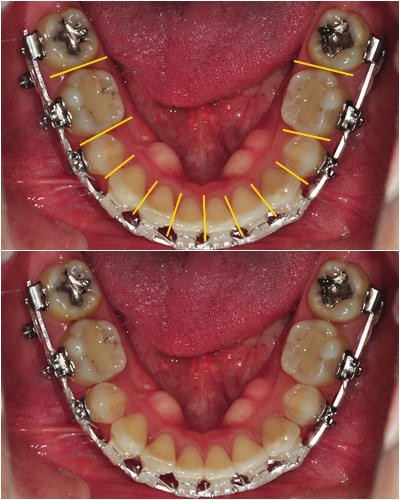

짜쟌~ 위에 사진처럼 치아 틈새마다 조금씩 갈아 주었어요~

아래 사진에 보시다시피... 정말 조금씩 얇게 갈아 낸 거라 티가 거의 안 나요~ ' ㅅ')!

상악에 맞는 크기로 맞춰주기 위해 하악 치아 사이 사이를 조금씩 갈아 주었어요~ ^^

30번째 월치료 때도 하악 치아 앞 부분을 조금씩 더 갈아 주었어요~

그 결과~ 상악 하악 일직선으로 맞물리던 앞니였는데~

하악 치아 갈아내고 나니 상악 치아가 하악 치아를 덮을 수 있게 되었어요~ ^ ㅁ^

물론 어금니 교합도 잘 맞아서 음식 씹기 편해졌구요~ >>ㅑ오~ 신나네요 ~('ㅅ '~)